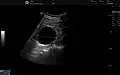

Non-contrast CT (at left) showing peripelvic fluid accumulations, which may be hydronephrosis. CT urography (at right) reveals non-dilated calyces and pelvises. The fluid accumulations are thus peripelvic cysts.

Parapelvic cysts originate from around the kidney at the adjacent renal parenchyma, and plunge into the renal sinus. Peripelvic cysts are contained entirely within the renal sinus, possibly related to dilated lymphatic channels. When viewed on CT in absence of contrast, they can mimic hydronephrosis.[15] If symptomatic, they can be laparoscopically decorticated - removal of the outer layer or cortex.[16]